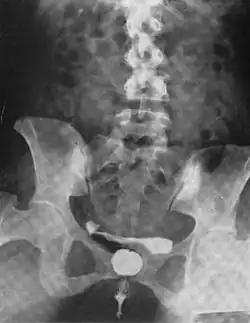

A urethral diverticulum seen on urethrogram

Urethral diverticulum is often an incidental finding.[2] It can be diagnosed using magnetic resonance imaging and/or micturating cystourethrography.[1] Other studies that can be used to diagnose urethral diverticulum include intravenous urography, urethroscopy, and/or ultrasound. Conditions that should be distinguished from urethral diverticulum in a differential diagnosis include overactive bladder, Gartner's duct cyst, Gartner's duct abscess, ectopic caeco-ureterocele, interstitial cystitis, pelvic inflammatory disease, endometriosis, and cancer.[3]